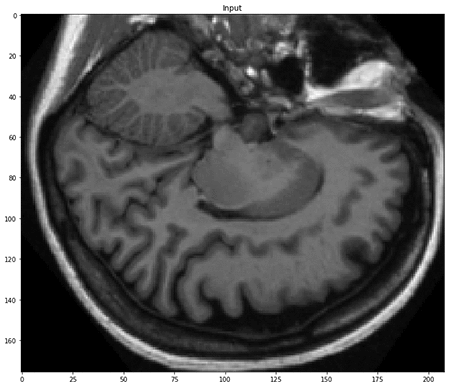

The data comes as a vector image in the .img format, each file representing a complete three-dimensional MRI scan of a particular brain. Although organ tissue segmentation is inherently a three-dimensional task, we approximate it by segmenting 2-D cross-sectional MRI slices. This is less complex and compute-intensive than volumetric segmentation and performs reasonably well.

First, load an example into memory as a numpy array and visualize a slice.

The array that we loaded into memory is three-dimensional as expected. We have selected a particular slice along the third axis, as shown in the following image.